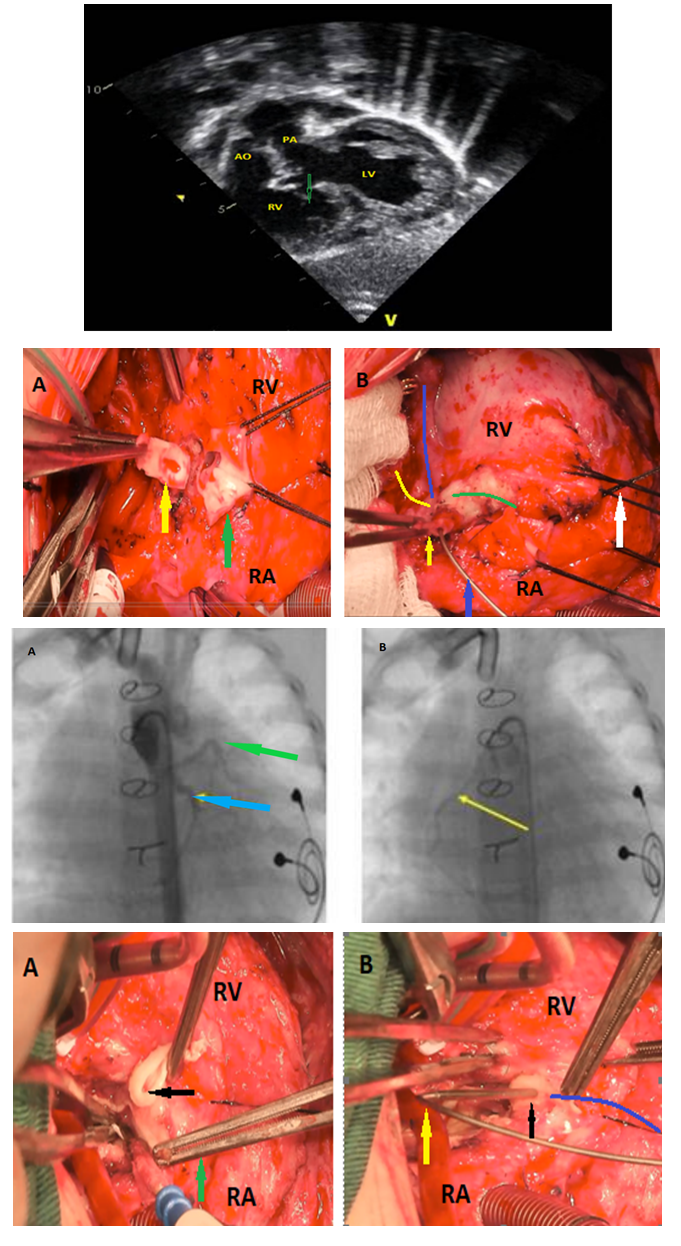

An Unusual Coronary Artery Complication after Surgery for a Complex Congenital Heart Disease: A Case Report

Zaher Faisal Zaher, MD